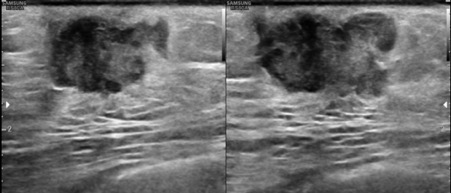

Bilateral Digital mammography , Craniocaudal (CC) and Mediolateral oblique (MLO) view revealed an irregular , high density mass with indistinct margin in retroareolar region with retracted nipple. No microcalcifications was seen. No significant axillary lymph nodes were present. Ultrasound of left breast showed an irregular, heterogeneously hypoechoic mass with indistinct margin and mild posterior acoustic enhancement, measuring about 2.5x1.9x1.3cm in retroareolar region. Internal vascularity was increased on colour doppler. On strain sonoelastogram, the mass showed increased stiffness suggestive of hard consistency. The imaging features are highly suspicious for male breast cancer and thus the mass was classified as BIRADS category 5 lesion and Ultrasound guided biopsy was advised. Patient underwent left modified radical mastectomy and final histopathological report was Invasive Lobular carcinoma. No nipple or lymphovascular invasion was identified.